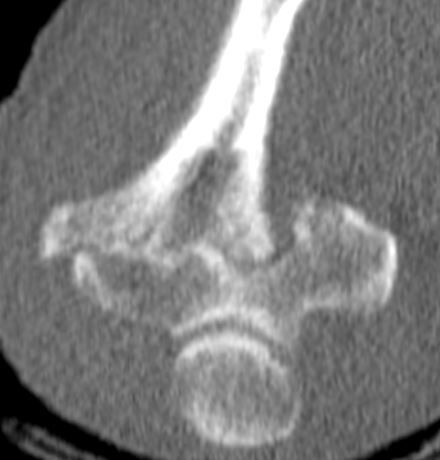

先日、高齢者の上腕骨通顆骨折の手術を施行しました。

基礎疾患に関節リウマチがあり、骨質はお世辞にも良いとは言えません。

周知のように高齢者の上腕骨通顆骨折は治療が難しいです。解剖学的に骨癒合を得ることが難しく、しかも関節拘縮をきたしやすいです。